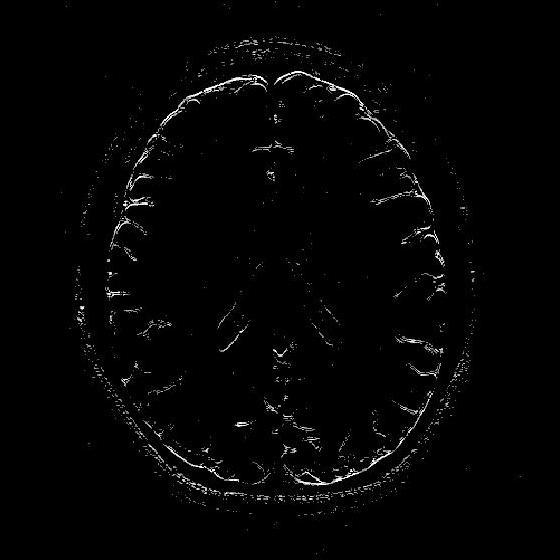

VII-D Application of the 2D-R-FFAST for MR imaging

Refer to caption

(a) Log intensity plot of the 2D-DFT of the original ‘Brain’ image. The red enclosed region is fully sampled and used for the stable inversion.

(b) Original ‘Brain’ image in spatial domain.

(c) Reconstructed ‘Brain’ image using the 2D-R-FFAST architecture along with the fully sampled center frequencies. The total number of Fourier measurements used is 60.18%percent60.1860.18\%.

(d) Log intensity plot of 2D-DFT of the original ‘Brain’ image, after application of the vertical difference operation.

(e) Differential ‘Brain’ image obtained using the vertical difference operation on the original ‘Brain’ image.

(f) Differential ‘Brain’ image reconstructed using the 2D-FFAST algorithm from 56.71%percent56.7156.71\% of Fourier measurements.

Figure 11: Application of the 2D-FFAST algorithm to reconstruct the ‘Brain’ image acquired on an MR scanner with dimension 504×504504504504\times 504. We first reconstruct the differential ‘Brain’ image shown in Fig. 11(e), using d=3𝑑3d=3 stage 2D-R-FFAST architecture with 151515 random delays in each of the 333 stages of the 2D-FFAST architecture. Additionally we acquire all the Fourier measurements from the center frequency as shown, by the red enclosure, in Fig. 11(a). Then, we do a stable inversion using the reconstructed differential ‘Brain’ image of Fig. 11(f) and the fully sampled center frequencies of Fig. 11(a), to get a reconstructed full ‘Brain’ image as shown in Fig. 11(c). Our proposed two-step acquisition and reconstruction procedure takes overall 60.18%percent60.1860.18\% of Fourier measurements.

In this section, we apply the 2D-R-FFAST algorithm to reconstruct a brain image acquired on an MR scanner with dimension 504×504504504504\times 504. In MR imaging the measurements are acquired in the Fourier domain and the task is to reconstruct the spatial image from significantly less number of Fourier measurements [17]. To reconstruct the full brain image using 2D-R-FFAST, we perform the following two-step procedure:

• Differential space signal acquisition: We perform a vertical finite difference operation on the image by multiplying the 2D-DFT signal with 1e2πıωx1superscript𝑒2𝜋italic-ısubscript𝜔𝑥1-e^{2\pi\imath\omega_{x}}. This operation effectively creates an approximately sparse differential image, as shown in Fig. 11(e), in spatial domain and can be reconstructed using 2D-FFAST. Note, that the finite difference operation can be performed on the sub-sampled data and at no point we access all the input Fourier measurements. The differential brain image is then sub-sampled and reconstructed using a 333 stage 2D-FFAST architecture. Also, since the brain image is approximately sparse, we take 151515 delay sub-streams in each of the 333 stages of the 2D-FFAST architecture, instead of 333 delay sub-streams as in the exactly sparse case. The 2D-R-FFAST algorithm reconstructs the differential brain image using 56.71%percent56.7156.71\% of Fourier measurements.

• Inversion using fully sampled center frequencies: After reconstructing the differential brain image, as shown in Fig. 11(f), we invert the finite difference operation by dividing the 2D-DFT measurements with 1e2πıωx1superscript𝑒2𝜋italic-ısubscript𝜔𝑥1-e^{2\pi\imath\omega_{x}}. Since the inversion is not stable near the center of the Fourier domain, only the non-center frequencies are inverted. The center region of the 2D-DFT is fully sampled and used in the inversion process.

• Overall we use a total of 60.18%percent60.1860.18\% of Fourier measurements to reconstruct the brain image using the 2D-R-FFAST algorithm along with the fully sampled center frequencies. The resulting signal-to-noise ratio of the reconstructed image is 4.51734.51734.5173 dB. While the reconstruction error is not as good as state-of-the-art compressed sensing MRI results, we note that the 2D-R-FFAST has both low computational complexity and low sample complexity , which none of the state-of-the-art compressed sensing results in MRI can achieve.